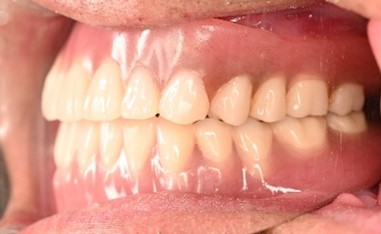

After

【義歯を装着したところ】

【義歯を外したところ】